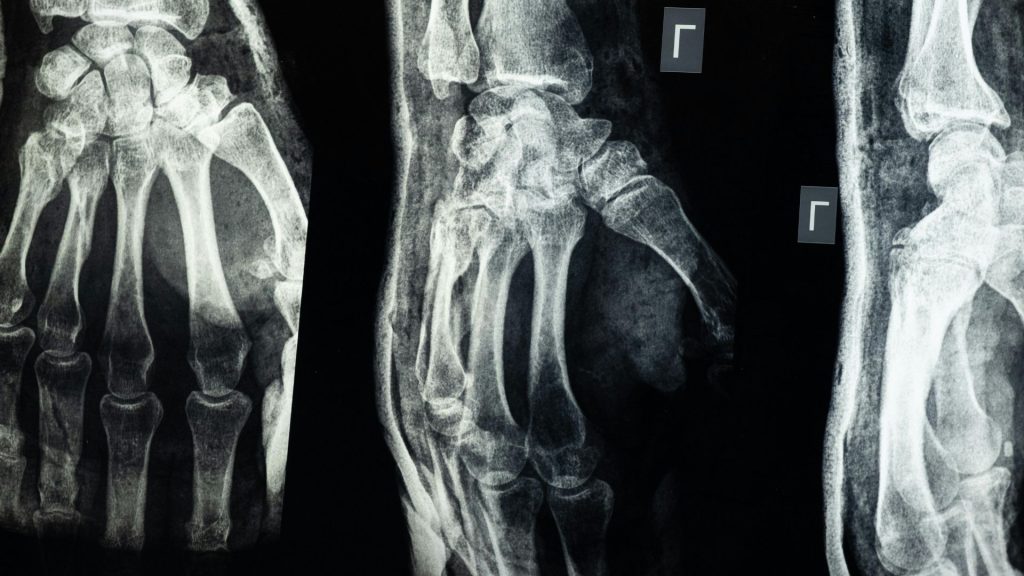

Menelisik Peran Kunci Radiologi Muskuloskeletal dalam Diagnosis Gangguan Gerak

Radiologi muskuloskeletal merupakan subspesialisasi krusial dalam dunia kedokteran yang berfokus pada pencitraan dan diagnosis gangguan yang melibatkan sistem pergerakan tubuh. Subspesialisasi ini mencakup studi mendalam terhadap tulang, sendi, otot, ligamen,…